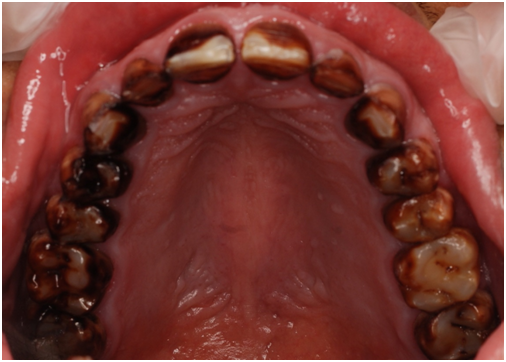

A 22 Yemeni male patient presented to the College of Dentistry clinics at the University of Dammam seeking cosmetic treatment with a chief complaint “I want to improve the way my teeth look " He reported no significant medical history. Patient has never been into the dental clinic. He stated his deciduas teeth were normal and his whole village complains of darkened teeth (brownish). A panoramic x-ray (Figure 1), intraoral pictures (Figures 2−6) as well as study casts were taken to diagnose the case (Figure 7). Upon examination, the patient was found to suffer from severely generalized discoloration of permanent teeth and moderate dental attrition resulting in shortening of the vertical dimension of occlusion (VDO). A class I occlusion with class I canine relation was present, with an over-bite of 4mm and an overjet of 4mm. The upper lip seems stretched with dropping mouth angles. The patient suffers from generalized marginal chronic gingivitis with no mobility or furcation involvement noticed. The treatment plan started with plaque control measures were conducted as well as patient education. The patient's esthetic problem caused by Fluorosis both teeth staining and facial appearance and occlusion. The treatment options available range from bleaching, porcelain veneers, full coverage ceramic crowns or porcelain fused to metal crowns. Due to the Fluorosis severity, the bond strength of the adhesive agent was questionable that eliminated the veneers option. Bleaching when tried had minimal effects. Finally, porcelain-fused to metal (PFM) crowns were selected to restore esthetics of anterior teeth, while posterior gold crowns were chosen to raise the occlusion posterior by 2mm. Treatment options were discussed with the patient who consents to the treatment plan.

Figure 3 Pre op upper arch.

Figure 4 Pre op lower arch.